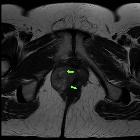

Vulvar

leiomyosarcoma in Bartholin"s gland. Axial T2 TSE. Relative isointense mass centred in the right vulva, replacing the labia majora and showing central areas of hyperintensity (green arrows).